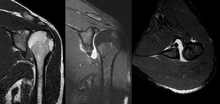

A diagnosis of shoulder dislocation is often suspected based on patient history and physical examination. Radiographs are made to confirm the diagnosis. Most dislocations are apparent on radiographs showing incongruence of the glenohumeral joint. Posterior dislocations may be hard to detect on standard AP radiographs, but are more readily detected on other views. After reduction, radiographs are usually repeated to confirm successful reduction and to detect bony damage. After repeated shoulder dislocations, an MRI scan may be used to assess soft tissue damage. In regards to recurrent dislocations, the supine apprehension test is a useful test in determining athletes who are predisposed to future dislocations.

- An anterior dislocation of the shoulder

Anterior dislocation of the right shoulder. AP X ray

Anterior dislocation of the right shoulder. Y view X ray.